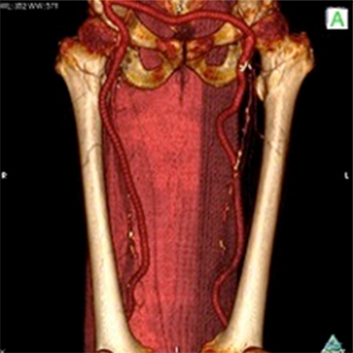

<手術前>両側総腸骨動脈(お腹の中にある足のつけねの動脈)と両側大腿動脈(太ももの動脈)に閉塞、狭窄部位があり、運動障害(間歇性跛行)や皮膚障害(壊死)を引き起こし、車椅子に乗られての入院となりました。

<手術後>右の鎖骨下~腋窩動脈(鎖骨の下から脇の下にかけての動脈)から両側大腿動脈、さらにそこから両側膝窩動脈(膝の裏の動脈)にバイパス手術を施行しました。

運動障害、皮膚障害も改善し、歩いて退院されました。

右鎖骨下〜膝窩動脈吻合

両側総腸骨動脈吻合部

両側大腿動脈吻合部